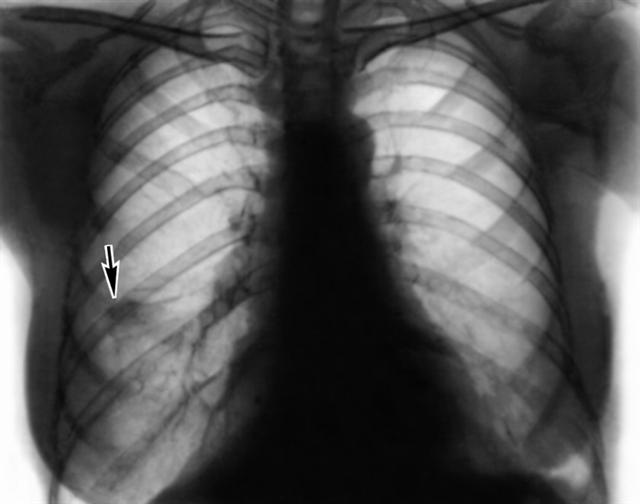

Рис. 1а). Рентгенограмма грудной клетки (прямая проекция) больного с эозинофильными летучими инфильтратами — одиночный инфильтрат в правом легком (указан стрелкой).